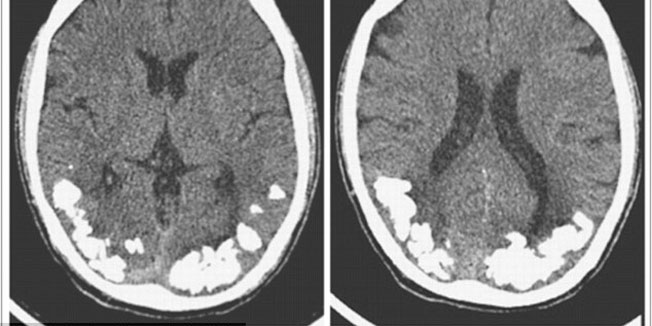

Nove injekcije daju nadu stotinama tisuća ljudi koji pate od kroničnih migrena, jedne od najtežih oblika glavobolja. Migrenski napad uzrokuju tzv. CGRP peptidi koji izazivaju bol, mučninu i povraćanje kod migrene a novi lijek, također bjelančevina, djeluje tako da se veže uz te peptide i 'pomete ih'.

CGRP se stvara u migreni i izaziva oticanje oko krvnih žila u blizini trigeminalnog živca. To dovodi ...